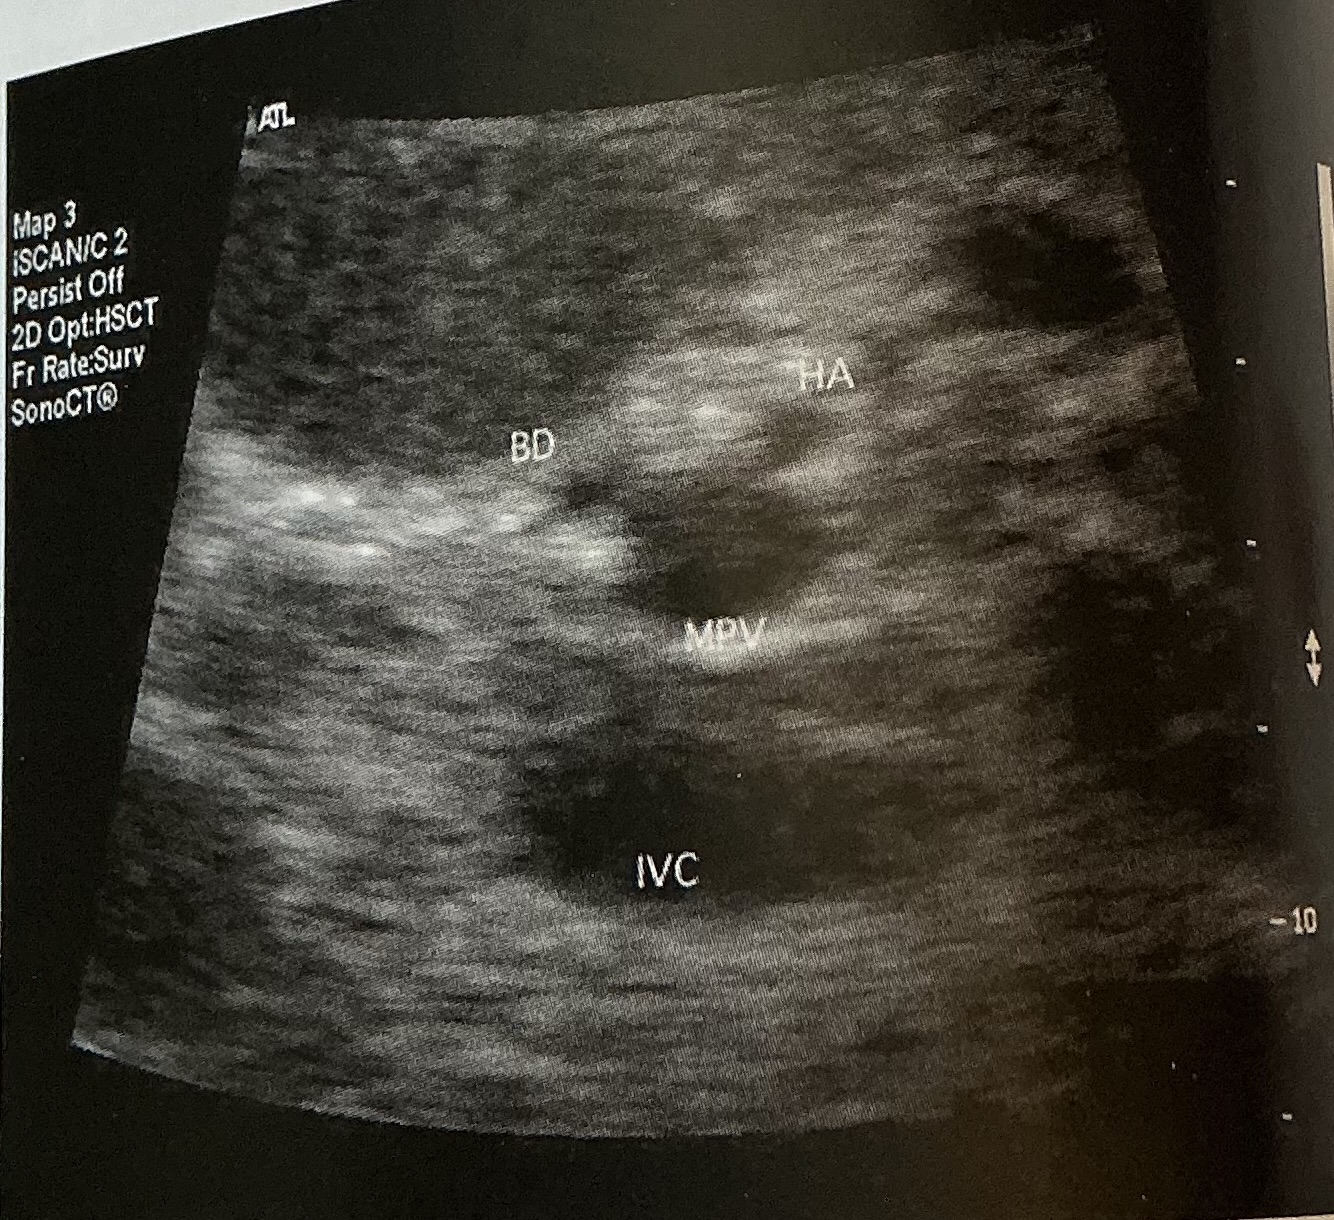

Mickey mouse sign

What is the normal diameter of the bile duct? What is the normal diameter of the hepatic artery?

bile duct: 4-8mm

Hepatic artery: 2-6mm